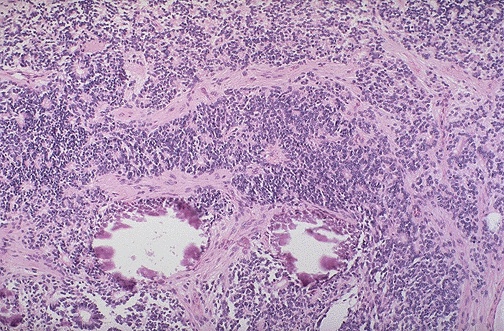

Retinoblastoma is one of the "small blue cell tumors" of childhood. Necrosis and dystrophic calcification are common histologic findings within this tumor. At low magnification, two small calcifications can be seen below center.